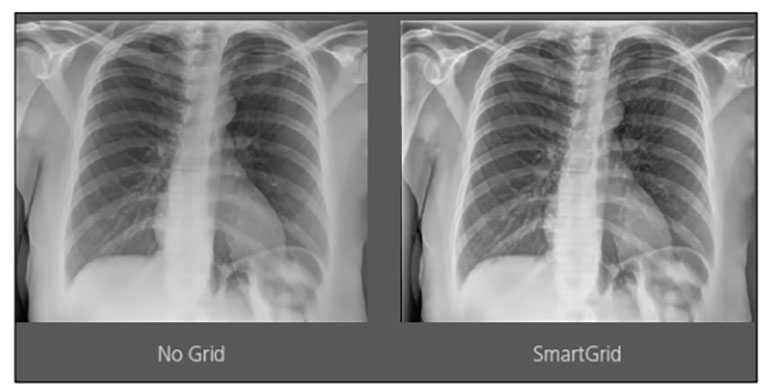

Our Carestream Focus HD 35/43 Retrofit Detectors, powered by Image Suite Software, are an ideal solution to step up to full digital X-ray for customers who simply cannot compromise on image quality. It seamlessly integrates into existing setups, bringing the power of full digital X-ray with minimal disruption and maximum clarity, along with the following benefits: